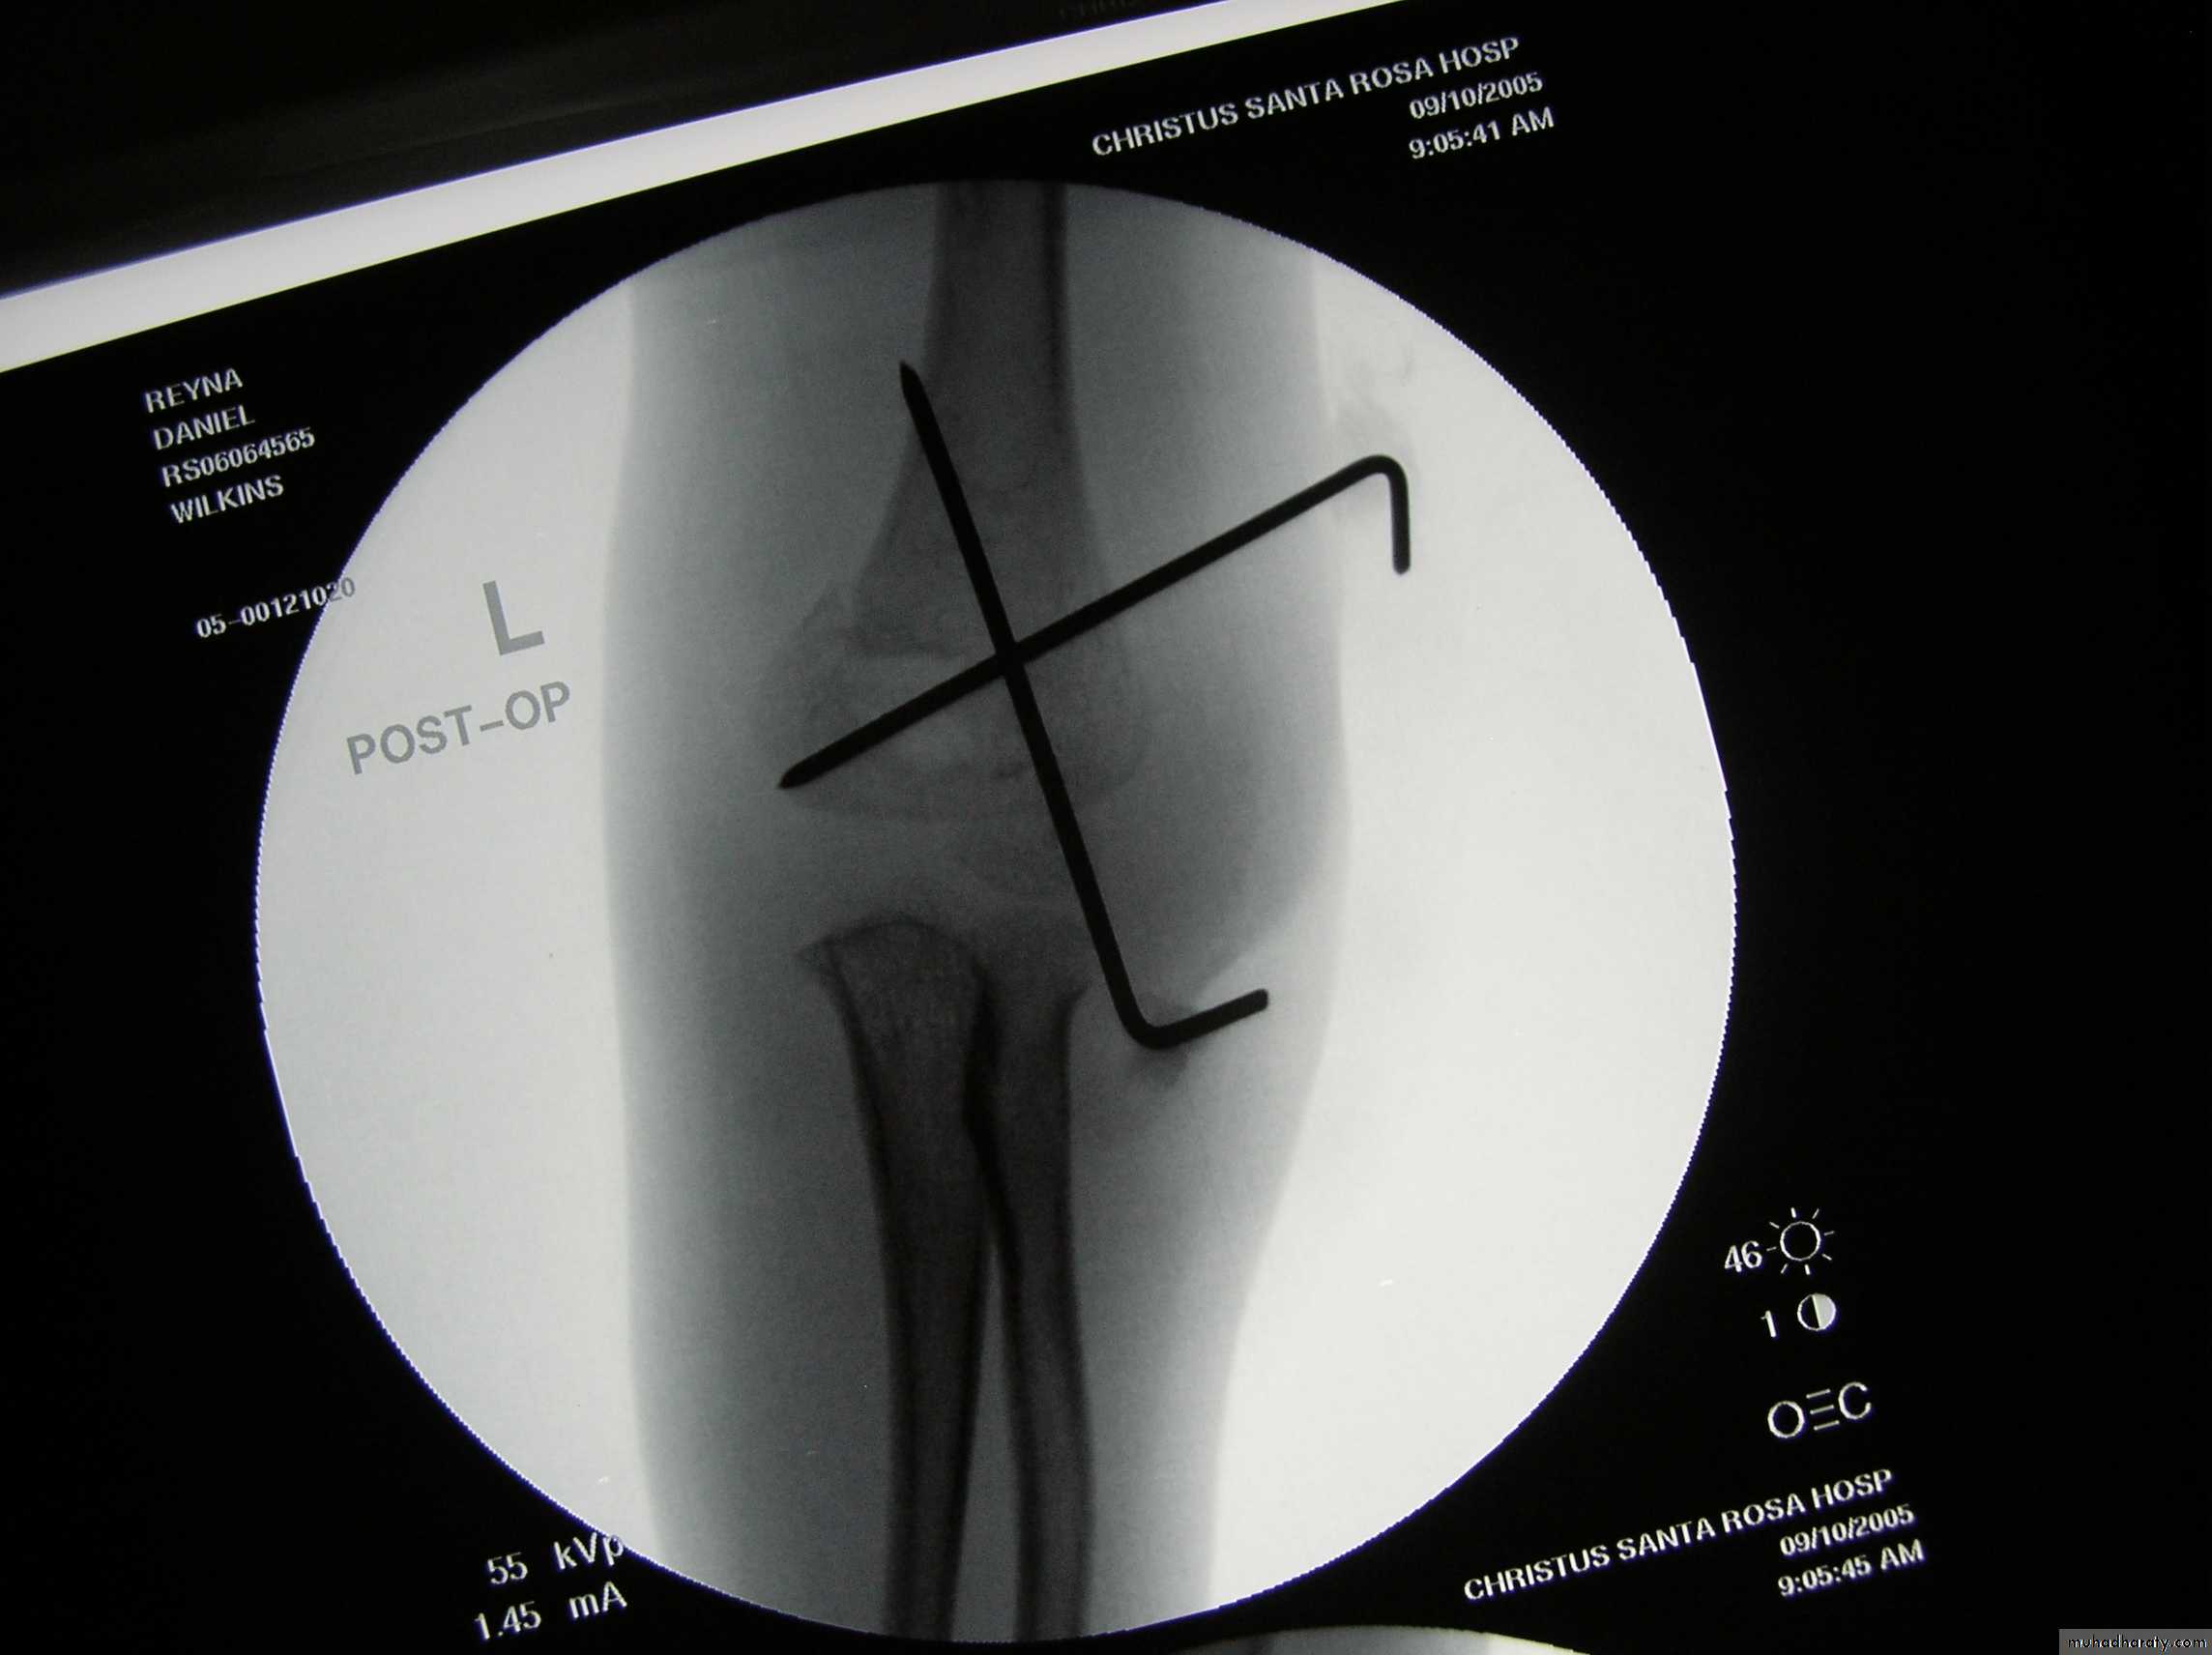

Following obtaining a satisfactory closed reduction how do you propose to stabilize it?• Medial-lateral pins

6 y.o. sustained this FX. NV intact.

Following obtaining a satisfactory closed reduction how do you propose to stabilize it?Multiple lateral pins

Outside fracture line ?6 y.o. sustained this FX. NV intact.

Following obtaining a satisfactory closed reduction how do you propose to stabilize it?

Cross pinsantegrade lateral